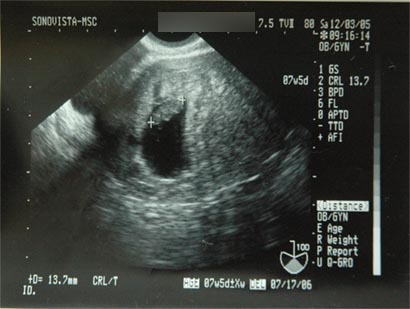

𝗽𝗶𝗽𝗶 𝟮𝟲𝘄 胎芽見えない 枯死卵かもって悩んでる方がいるかもなのでまとめておこう 4w0d 胎嚢 1 2mm程度 5w0d 胎嚢 12 4mm 卵黄嚢確認 6w0d 胎嚢 21 6mm 胎芽 卵黄嚢見えず 7w0d 胎芽 11 2mm 心拍確認 6w0dに中身